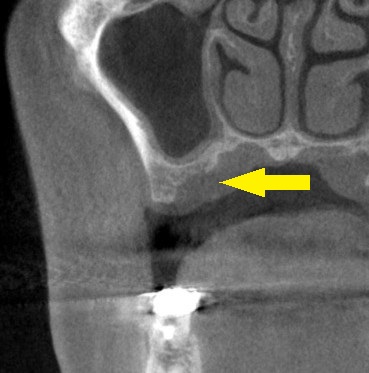

下の写真、上段の単純レントゲン写真では、骨の高さがあるように見えましたが、CTを撮影してみると、下段左の写真のように、骨の形が不整で、インプラントを埋入するには、内側の骨が不足していました。

そこで、内側に、人工骨を補填して骨を増大する手術を併用してのインプラント埋入手術を、提案させていただきました。